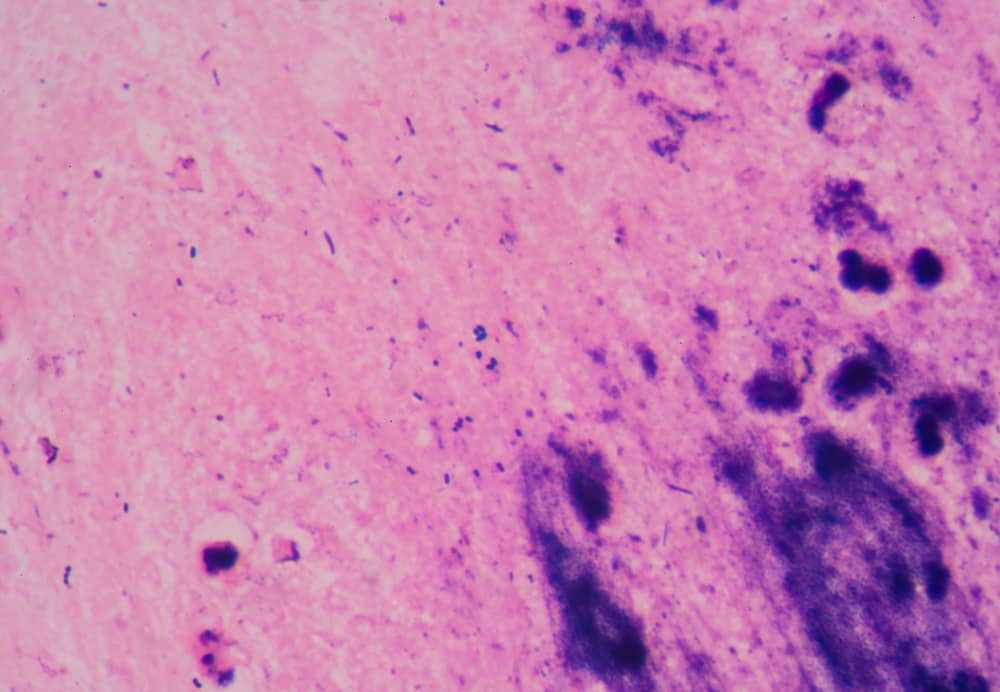

Khi quan sát dưới kính hiển vi kỹ thuật viên có thể thấy vi khuẩn lạ xuất hiện dẫn đến nhầm lẫn giữa gram dương và gram âm hoặc phát hiện vi khuẩn không có thật trong bệnh phẩm.

Những vi khuẩn này sau đó bám vào slide mới trong quá trình ngâm, tạo ra vi khuẩn ma trên kính hiển vi. Tạp khuẩn loại 2 thường gây ra tình trạng nhuộm không đồng đều, màu sắc bị lẫn lộn hoặc xuất hiện vi khuẩn lạ không thuộc mẫu bệnh phẩm.

Khi tạp khuẩn xuất hiện kết quả nhuộm gram có thể sai lệch hoàn toàn. Ví dụ gram dương bị nhầm thành gram âm hoặc ngược lại dẫn đến chẩn đoán sai bệnh. Bác sĩ có thể kê đơn kháng sinh không đúng kéo dài thời gian điều trị hoặc thậm chí gây hại cho bệnh nhân.